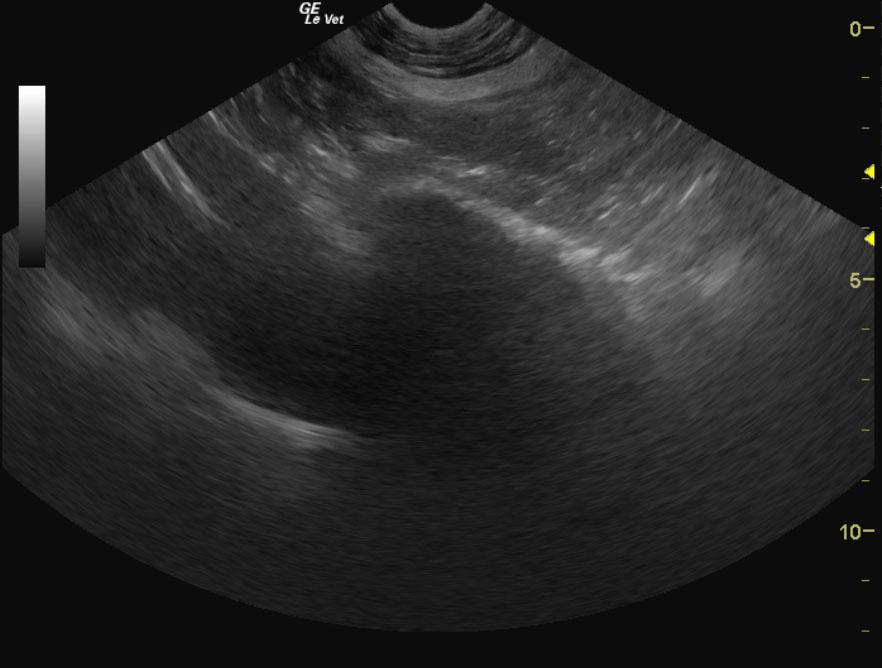

A 10-year-old FS Bull Mastiff dog with a history of urinary tract infections was presented for vomiting, polyuria/polydypsia, and pollakiuria. The urine appeared turbid, and analysis revealed isosthenuria, proteinuria, pyuria, and hematuria. Urine culture yielded E.coli. Abnormalities on CBC and serum biochemistry were monocytosis, mildly elevated ALP activity, and elevated lipase.